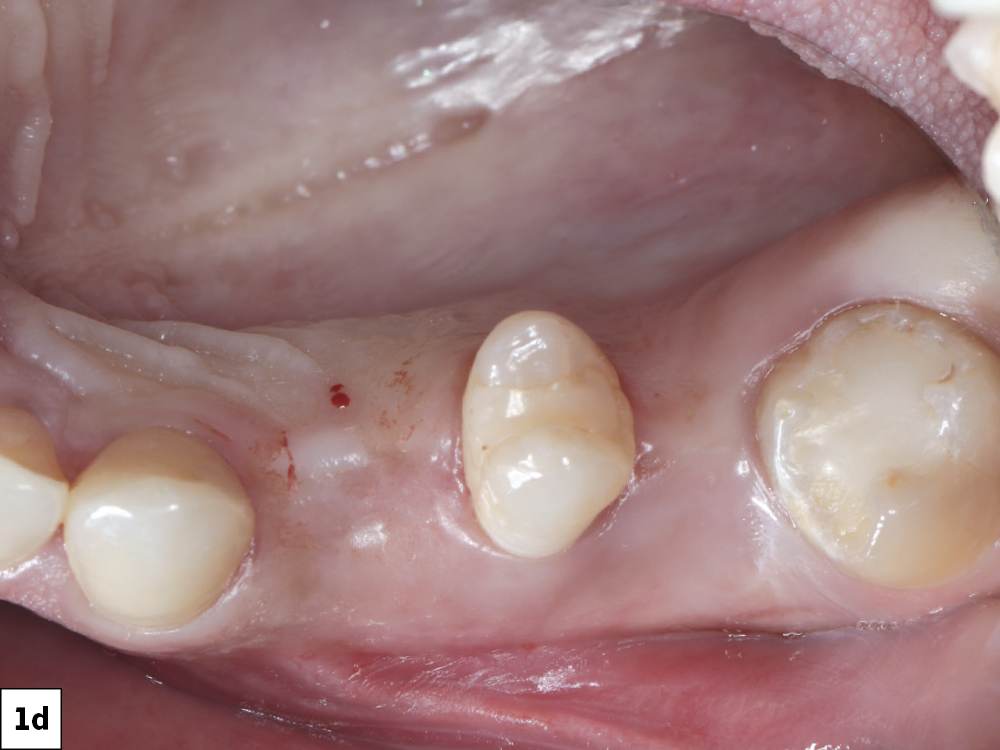

She had no medical contraindications and expressed a strong desire for a rapid restoration of her smile

Both sides had healed from previous extractions. Site #5 exhibited sufficient bone width and height for immediate implant placement

Figures 1a–1d: A young, healthy female patient presented with two edentulous premolar sites in the areas of teeth #5 & #12. She had no medical contraindications and expressed a strong desire for a rapid restoration of her smile. Both sides had healed from previous extractions. Site #5 exhibited sufficient bone width and height for immediate implant placement, while site #12 presented with a thin buccal plate that required simultaneous grafting to enhance ridge contour and long-term stability. The patient’s motivation and the precision afforded by guided surgery made this an excellent case for a same-day digital implant workflow incorporating immediate bone augmentation.